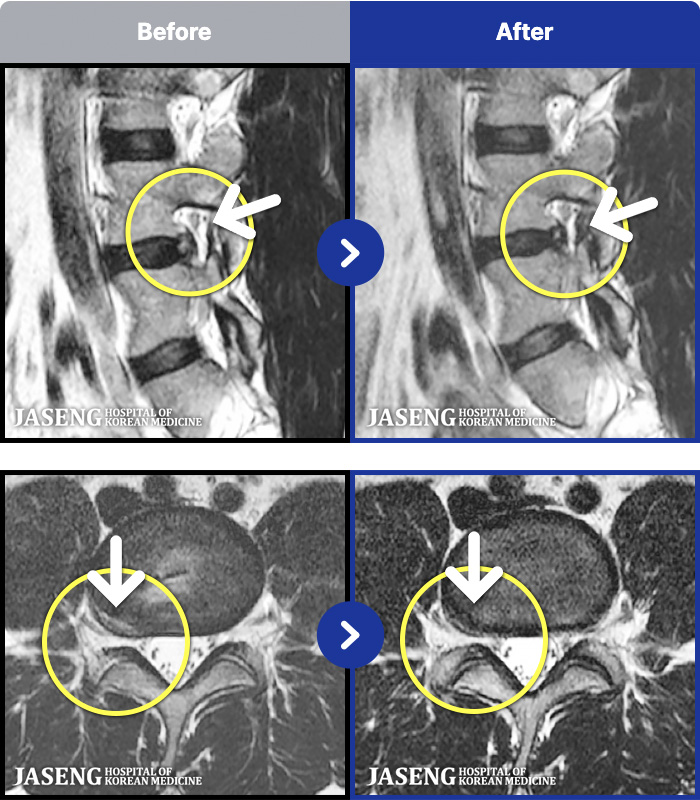

1,299 MRI ũ ʸ Ȯϼ.

[] 23.11.11~25.06.04